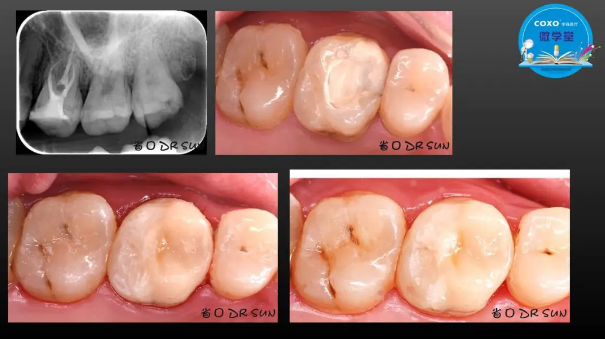

主任醫(yī)師,牙體牙髓副主任, 廣東省口腔醫(yī)院牙體牙髓科 主任醫(yī)師。2003年碩士研究生畢業(yè),研究方向?yàn)檠荔w牙髓病學(xué),擅長(zhǎng)于牙體牙髓病的診斷、齲齒、牙髓炎、根尖周病的治療以及前牙美容修復(fù)。